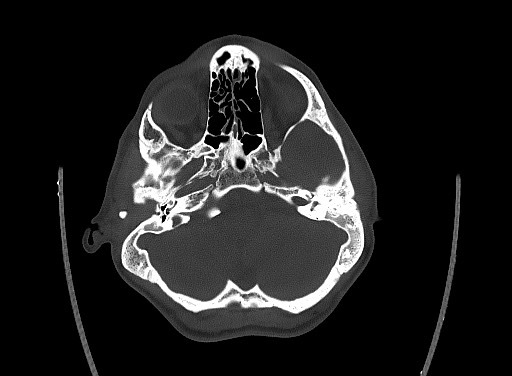

cochlear aplasia

The labyrinth is abnormal with the cochlear absent (cochlear aplasia). The vestibule, semicircular canals and ossicles are present.

Cochlear aplasia, or complete absence of the cochlea is a rare anomaly which accounts for only 3% of cochlear malformations.